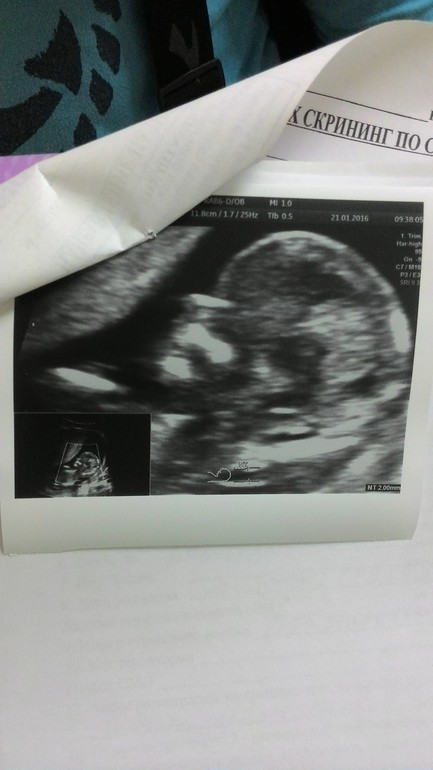

Потом уже крошечного человечка 8 см длиной:

И вот уже осталось совсем немного, около 9 недель всего)))) Кстати, о страхе родов. Я не боюсь! Вот абсолютно! Я ожидаю этого с чувством трепета и внутреннего дрожжания (но не от страха, а от восторга). Это будет как вход в новую жизнь, это как перепрыгнуть пропасть, а там будет мой сынок, мое счастье))) Но когда я отвечаю на вопросы окружающих "Ну как, боишься рожать?" - "Ни капельки!" люди смотрят на меня как на душевнобольную, потом сочувственно улыбаются, хлопают по плечу и считают своим долгом сказать что-то типа "Ну-ну... подожди, еще накроет, вот приедешь в роддом, ТАК затрясет, мало не покажется".. И начинают рассказывать очередную страшилку про адские боли, кровотечения, гипоксию плода, реанимацию, родовые травмы, потери сознания в родах и прочее... У вас так же? Или они правы, и я действительно витаю в облаках? Нет, я знаю, что будет больно, возможно адски больно, но я так же знаю, что я все вытерплю, все смогу, все сделаю ради своего малыша! Да, возможно, уже в роддоме меня "накроет", но сейчас то зачем трястись и пугать себя и ребенка?)))))